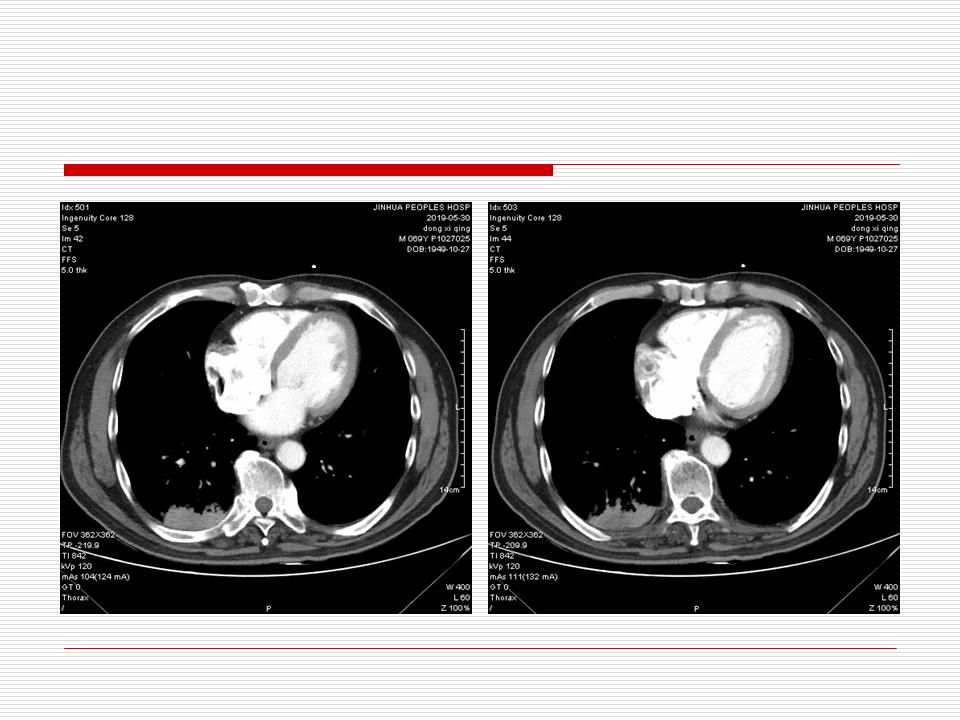

肺部阴影永恒且最重需要鉴别的是:到底是炎症还是肿瘤?但临床的病例中的影像表现难以界定或有些肿瘤特征,同时又有些炎症特点是非常常见的情况。作为临床医生我们怎么去总结分析,并找到之所以是炎症或之所以是肿瘤的细微差别或特点非常重要,也非常有用。2019.12.7浙江省2019年胸心外科学学术年会在宁波召开时,我的临床病例分析与经验总结<那些像肺癌的炎症与像炎症的肺癌>获得在大会交流的机会,以下为该PPT的内容,与你分享,希望对同道有益,有借鉴与启迪。若有探讨与进一不完善的建议,欢迎文末留言讨论: